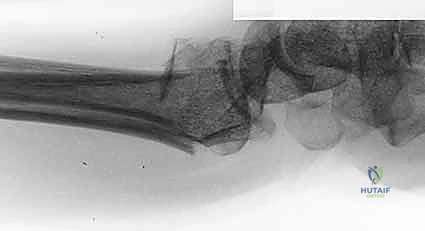

- الأشعة السينية (X-rays):

هي الخطوة الأولى لتقييم الكسر. يتم أخذ صور من زوايا متعددة (أمامية خلفية، جانبية، ومائلة) لتحديد موقع الكسر الأساسي ودرجة الانزياح والتقصير في عظم الكعبرة.

- التصوير المقطعي المحوسب (CT Scan) مع إعادة البناء ثلاثي الأبعاد:

هذا هو المعيار الذهبي الذي يعتمده الدكتور هطيف لجميع كسور المفصل المعقدة. تتيح الأشعة المقطعية رؤية كل شظية عظمية بوضوح تام، وتحديد حجمها، وموقعها، ودرجة تفتت السطح المفصلي بدقة ملليمترية. من خلال إعادة البناء ثلاثي الأبعاد (3D Reconstruction)، يمكن للدكتور هطيف "رؤية" الكسر من جميع الزوايا قبل فتح الجلد، مما يسمح له باختيار الغرسات (الصفائح والمسامير) الدقيقة لكل شظية وتحديد المداخل الجراحية المثلى.